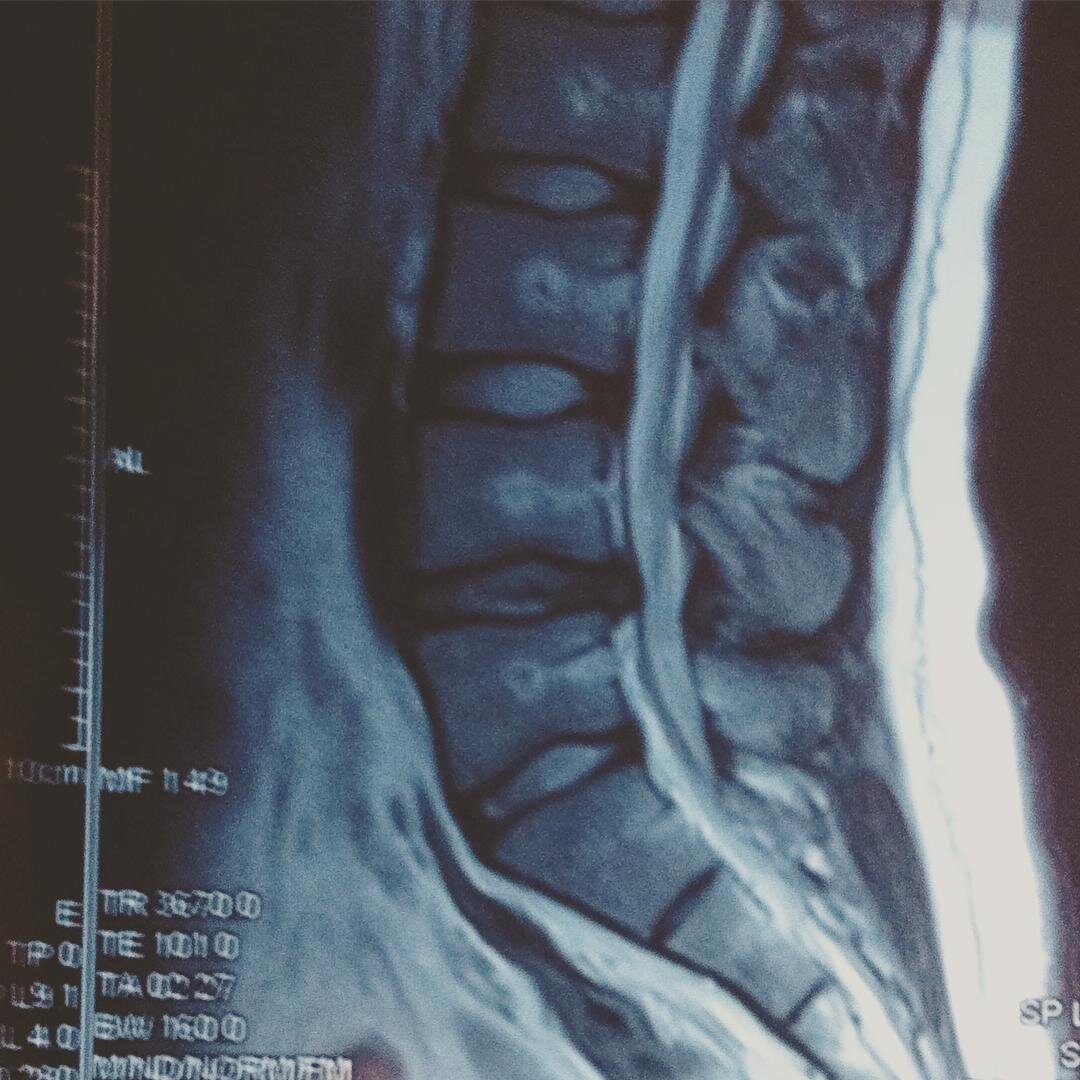

Но кто бы что не подумал, «прихватило» меня вовсе не на во время занятия спортом. Одним зимним вечером, я занимался ремонтом - стелил линолеум, пребывая в различных неудобных позах около двух-трёх часов. И вот разогнувшись, я понял – что-то не так. Боль в спине была не такая, как обычно и проходить она не собиралась. Через какое-то время при ходьбе стала периодически отказывать правая нога настолько, что какое-то время, сдвинуться с места не представлялось возможным (происходило защемление седалищного нерва). Я, конечно уже, прекрасно понимал, что это грыжа, что и подтвердили снимки МРТ поясничного отдела позвоночника.

Моя грыжа не большая, но и не маленькая, в районе 7-8 миллиметров, в поясничной области и в весьма неудачном месте. Естественно, мне посоветовали больше не соваться в качалку и забыть о больших весах (большие в понимании врачей, всё что больше 5 кг). Признаться, с тех пор я перестал практиковать работу с большими весами в упражнениях, где большая осевая нагрузка или большая нагрузка на поясничный отдел.